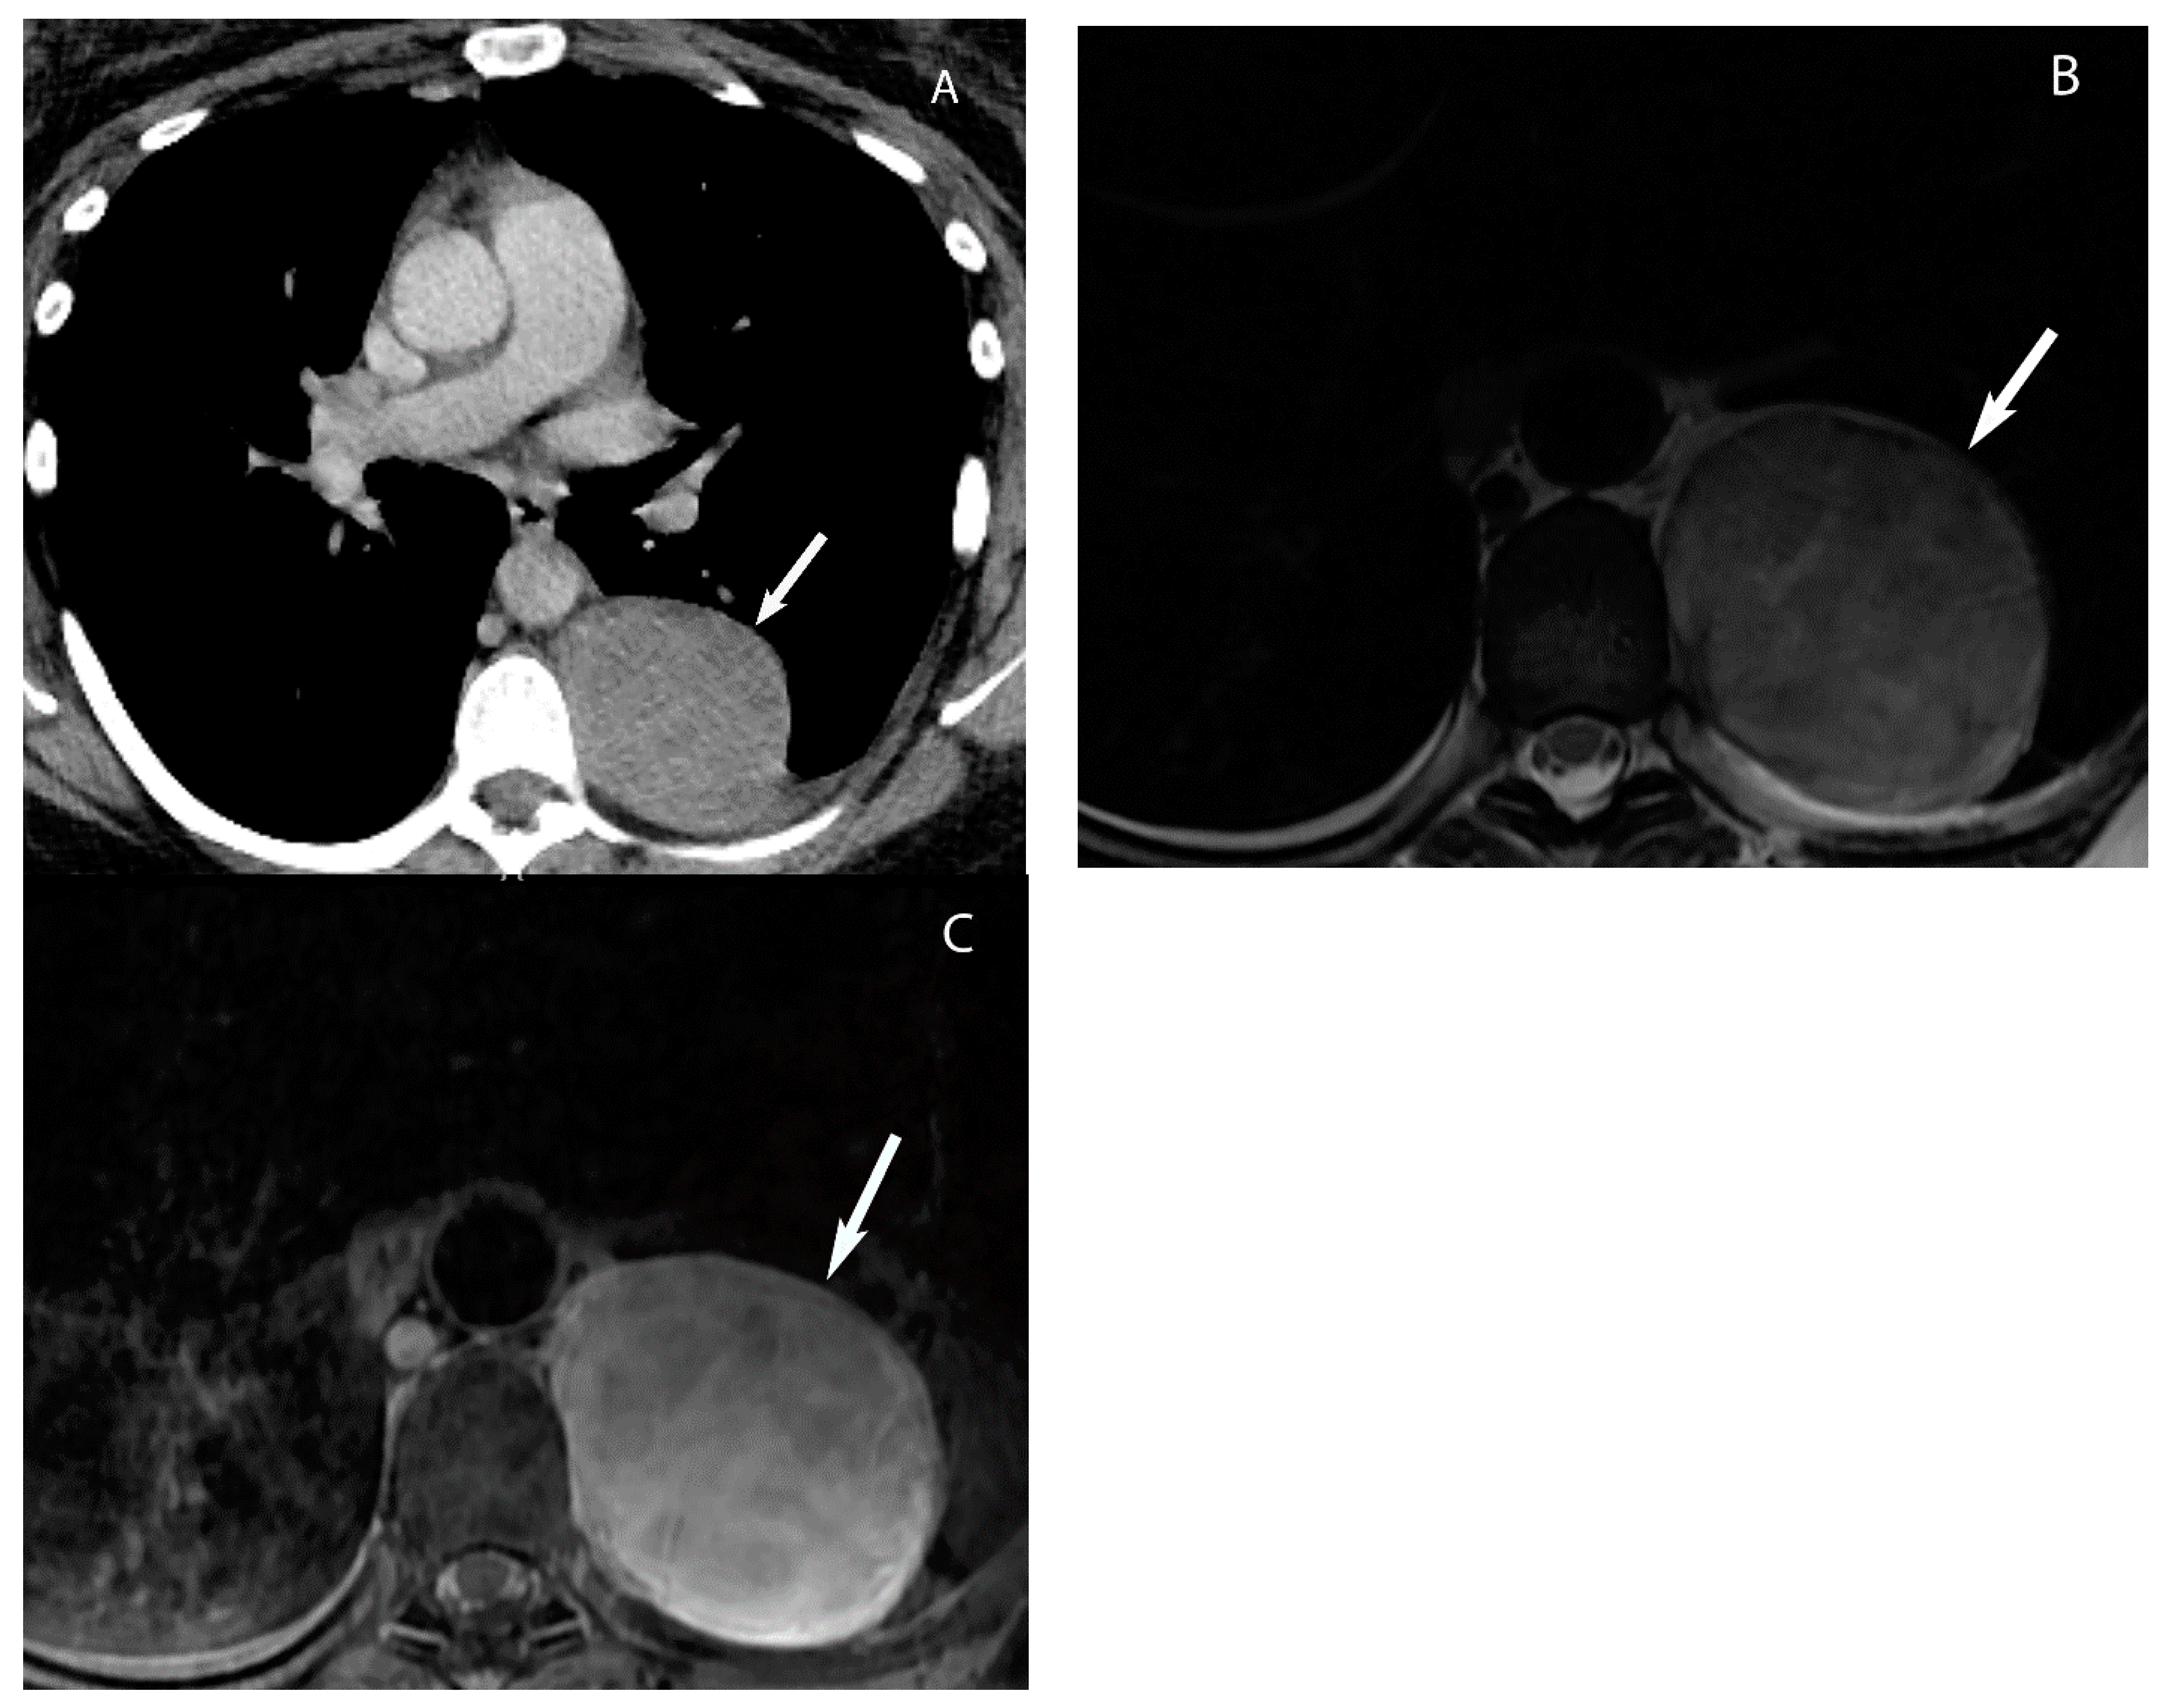

7. Germ Cell Tumors

9. Hypervascular Lesions